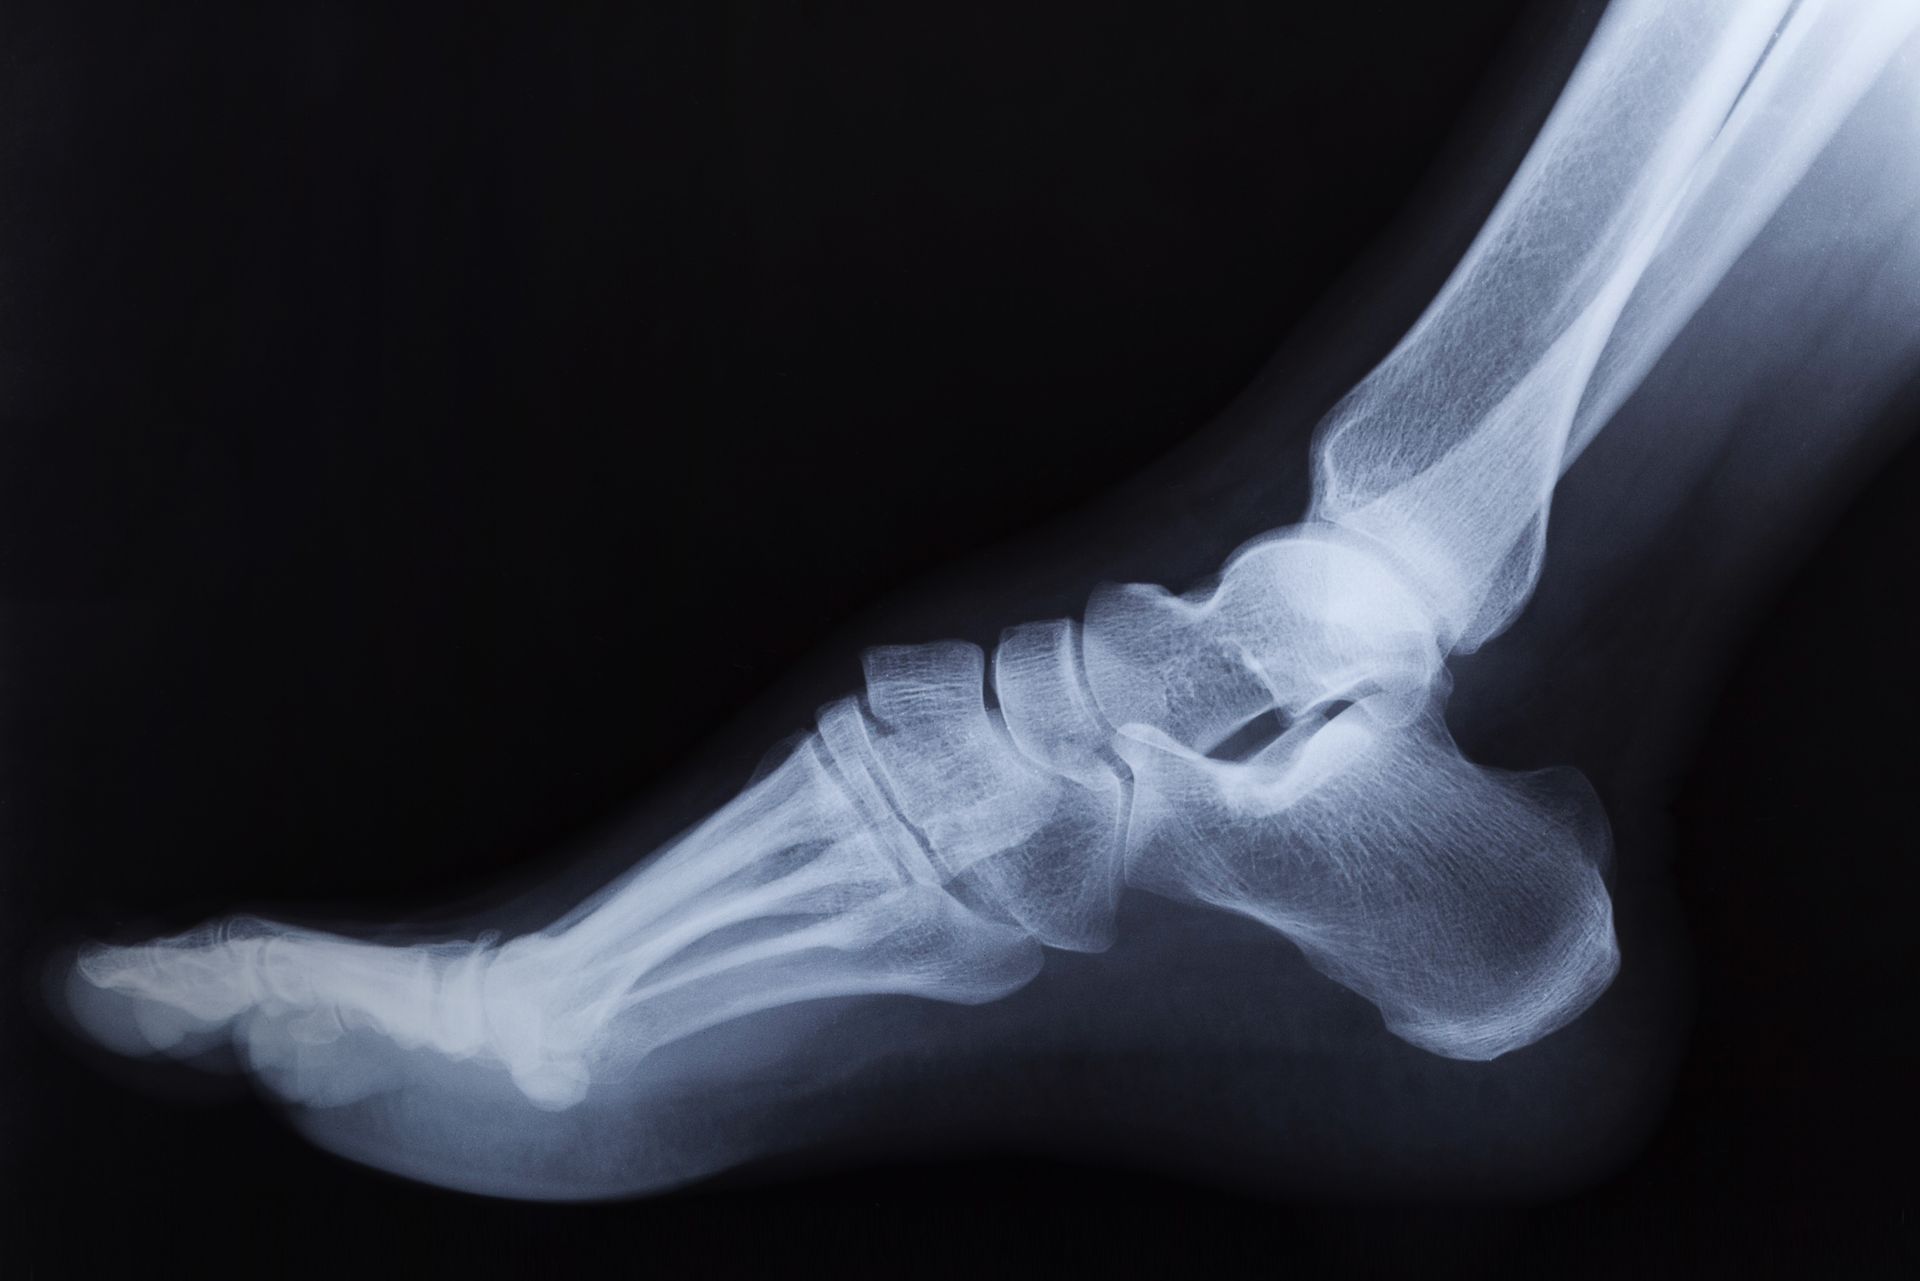

Effective Management of Heel Discomfort

Heel pain often restricts movement and can stem from multiple sources, including plantar fasciitis, Achilles tendonitis, heel spurs, or stress fractures.

Understanding Heel Pain Causes

• Plantar fasciitis due to inflammation of connective tissue.

• Achilles tendonitis from repetitive strain.

• Heel spurs developing from prolonged stress.

• Calcaneal stress fractures needing precise diagnosis.

Physical Therapy and Surgical Treatments

Initially, physical therapy, stretching routines, and orthotics address heel pain. When these are insufficient, surgical options provide relief, performed with expert precision to minimize downtime.